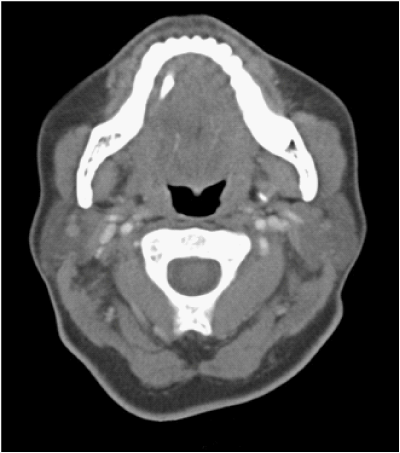

The CT showed a calculus in the region of distal submandibular duct measuring 5 X 3 X 13mm and evidence for acute inflammation (Figures 1&2). On further history taking, she has had no such similar episodes since the removal of her right submandibular gland and this was her first attack. She has also not noted any lump in her floor of mouth or neck in the past.

Figure 1 Computerised Tomography (CT) scan image of the patient showing the stone in the Wharton’s duct.